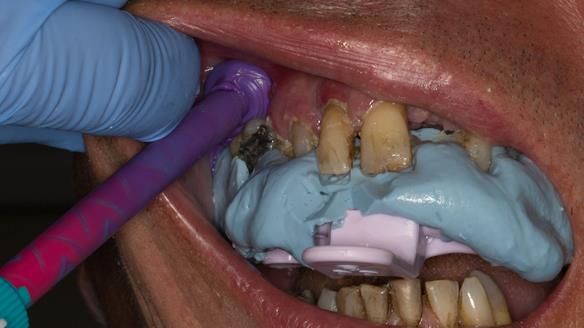

This newsletter describes in step by step detail the transition from acrylic based immediate dentures to metal based definitive dentures.

This 52 year old man was referred to me from his general dental practitioner in 2018.

The clinical situation and treatment process is shown in detail below with photographs.